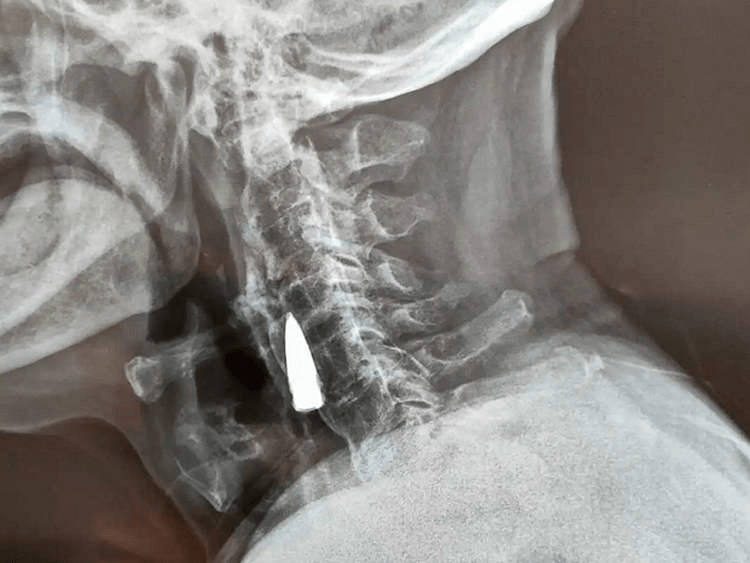

赵某在中国山东从自家阳台上摔了下来,直到他开始感到脖子有点不舒服,才真正出现了严重的症状。儿子看到了,就带他去医院请医生检查。当医生得知他摔倒的情况后,他们建议做x光检查,以排除摔倒造成的严重损害。出乎他们意料的是,他们在他的脖子上发现了一颗旧子弹!

赵自己估计,这颗子弹从1944年起就一直在他的脖子上,当时他在过河时被子弹击中。他声称,子弹穿过左鼻子,穿过他的上颚,打掉了四颗牙齿,然后卡在他的脖子上。

在检查了x光片后,医生告诉赵贺和他的家人,子弹靠近一些主要血管,因为它不会造成问题,他们建议把它留下。